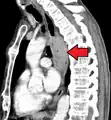

Esophageal cancer as shown by a filling defect during an upper GI series

Although an occlusive tumor may be suspected on a barium swallow or barium meal, the diagnosis is best made with an examination using an endoscope. This involves the passing of a flexible tube with a light and camera down the esophagus and examining the wall, and is called an esophagogastroduodenoscopy. Biopsies taken of suspicious lesions are then examined histologically for signs of malignancy.

Additional testing is needed to assess how much the cancer has spread (see #Staging, below). Computed tomography (CT) of the chest, abdomen and pelvis can evaluate whether the cancer has spread to adjacent tissues or distant organs (especially liver and lymph nodes). The sensitivity of a CT scan is limited by its ability to detect masses (e.g. enlarged lymph nodes or involved organs) generally larger than 1 cm.[41][42] Positron emission tomography is also used to estimate the extent of the disease and is regarded as more precise than CT alone.[43] Esophageal endoscopic ultrasound can provide staging information regarding the level of tumor invasion, and possible spread to regional lymph nodes.